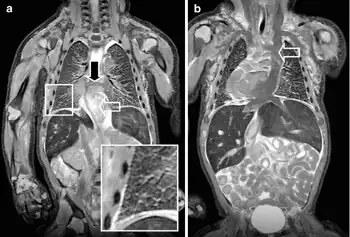

A neonate with a congenital cyanotic heart disease a)MRI shows a complete anomalous venous return b) T2-W coronal MRI shows a persistent left superior caval vein